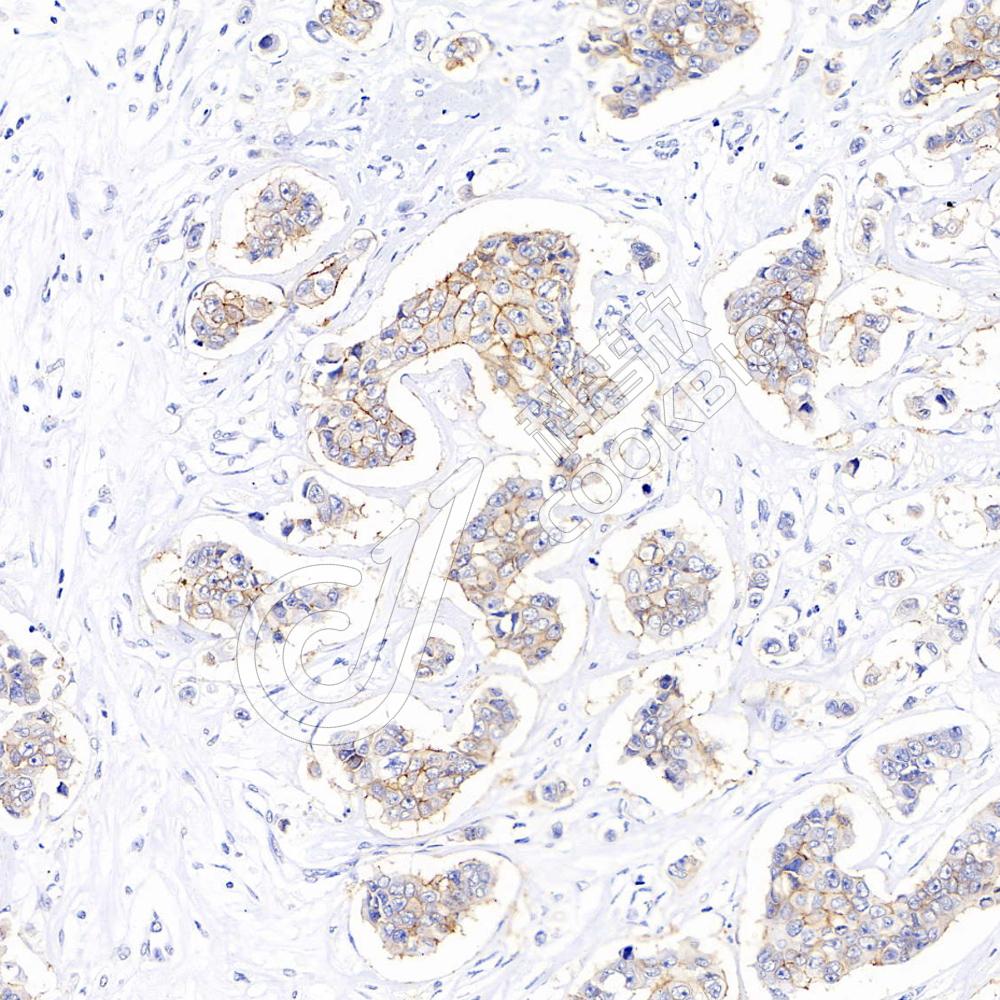

IHC检测ErbB2/HER2蛋白(货号 K236981).

样品: 人乳腺癌, 4%多聚甲醛 (货号KSG1101) 固定12-24小时.

抗原修复: 柠檬酸抗原修复液(干粉, pH 6.0) (KSG1201), 高压锅均匀喷气计时2分钟.

—抗: 1: 600稀释, 4℃ 孵育过夜.

二抗: S-vision免疫组化多聚二抗(山羊抗小鼠), 即用型(货号KB3903), 室温孵育20分钟.